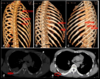

¿Qué es esto?

Tórax inestable